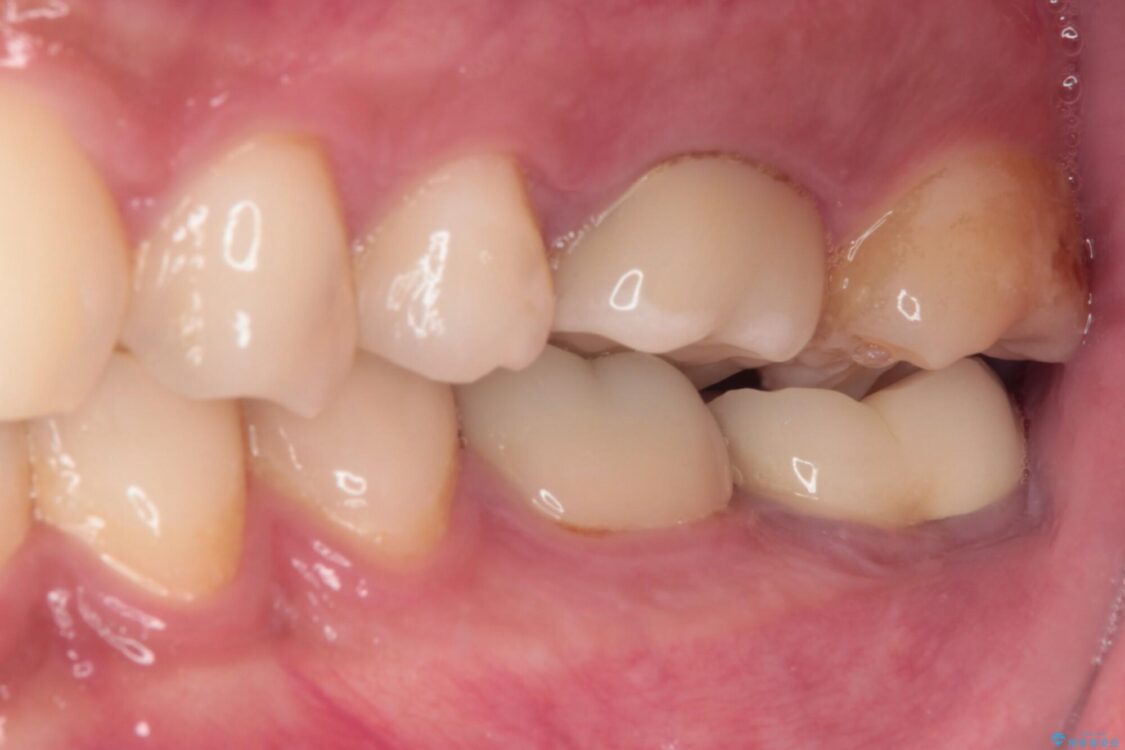

治療後について

十分な土台の高さを確保できない状態であったので、維持力のある土台の形態に整えることで、極力長持ちする治療を心がけました。

治療後

• 海外赴任前に治したい 割れてしまった奥歯のオールセラミッククラウン 治療後画像